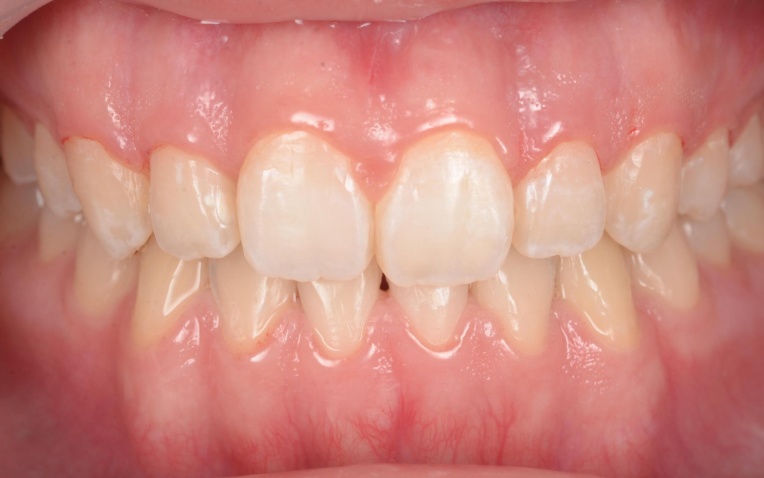

「前歯が噛み合わないので治したい」とご相談いただきました。 |

拝見したところ、重度の開咬(かいこう)が認められました。 |

見た目と噛む機能の両方を改善するため、矯正治療を提案し、同意いただきました。 |

18ヶ月 |